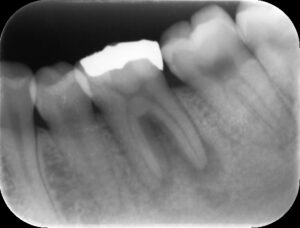

初診時レントゲン。虫歯治療で大きな詰め物が装着してあり、深い虫歯があったことがうかがえる。歯根の周りは骨吸収が起こり、歯髄壊死から継発した根尖病巣を生じている。根管治療が必要な状態。